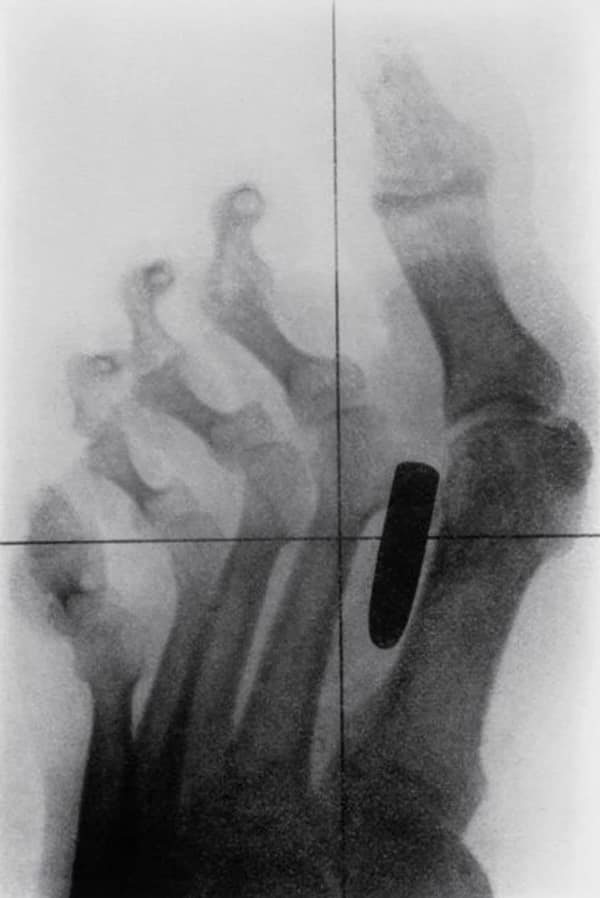

Weird xray photos

I used to think that nothing could surprise me anymore—until I stumbled upon some weird x-ray photos that made me reconsider my stance on human ingenuity (or lack thereof). Apparently, some people have a knack for getting objects lodged where they absolutely shouldn’t be. If you’ve ever wondered how not to use everyday items, these images might provide some unintended guidance.

This collection showcases 31 bizarre x-ray images that defy logic and anatomy textbooks alike. Each photo reveals unexpected objects making cameo appearances inside the human body, turning medical imaging into a gallery of the absurd. From common household items inexplicably found in unusual places to anomalies that would leave even seasoned doctors scratching their heads, these images offer a perplexing glimpse into the more “creative” side of medical emergencies. They highlight the intersection of curiosity, misadventure, and perhaps a dash of poor decision-making, all captured through the lens of radiology.